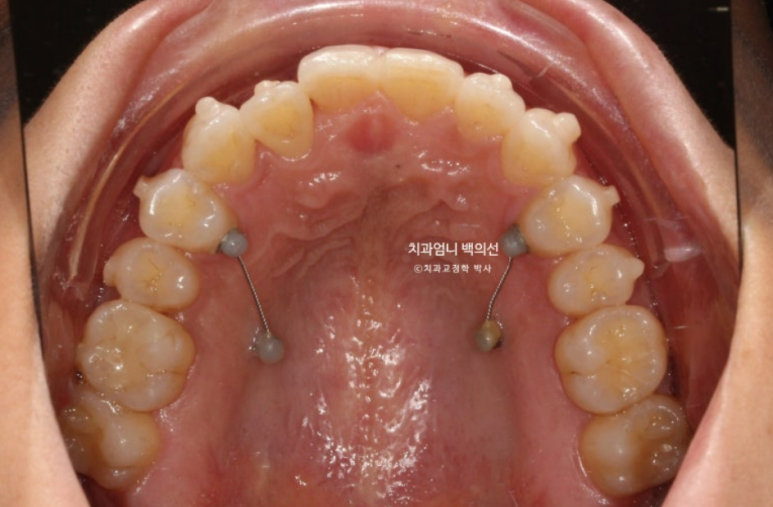

멀리서 오시기에 내원간격 때문에 인비절라인 치료를 선택하셨고 23년 10월부터 24년 8월까지 첫세트 44개 장치를 모두 낀 후 모습입니다

중심선은 잘 맞으나 입천장에 위치했던 축절치가 아직 완벽하게 제자리를 찾지 못했습니다.

덧니의 머리부분은 앞으로 잘 나와 있지만

교합면에서 보면 입천장에 위치했던 덧니 뿌리 부분은 아직 입천장 쪽에 위치해 있습니다.